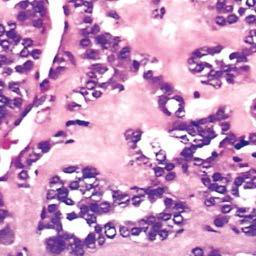

less common type of thyroid carcinoma that is composed of solitary “cold” nodules (ie, don’t take up radioactive iodine) and tends to metastasize to the lungs, bone and liver

follicular thyroid cancer

*note below the destruction of follicles, showing only remnants of thyroglobulin